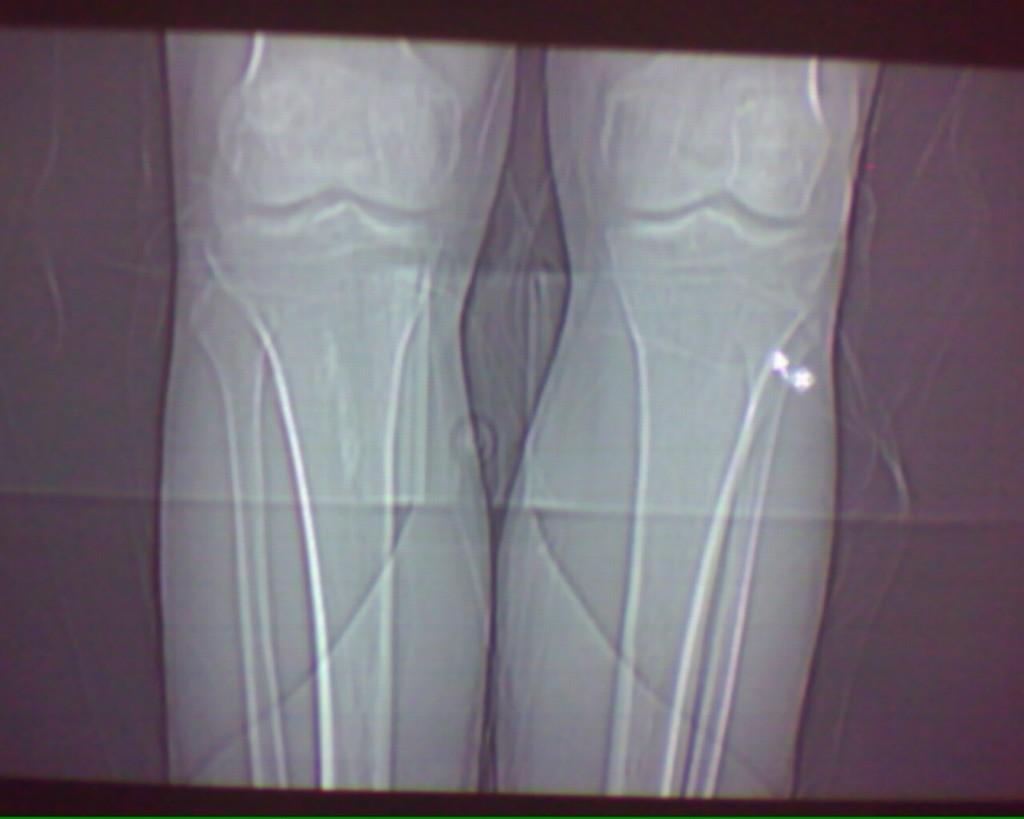

标题: CT19926:右胫骨上段高密度病变

男性,47岁,在一次外伤摄片中发现右胫骨上段条状高密度影,ct横断面上发现条状高密度影(钙化及骨化密度)位于胫骨皮质下,和皮质紧密相连,我考虑纤维性骨皮质缺损钙化可能性大,大家认为呢?大家注意看定位片,高密度病灶是很长的,横断面我只是选取了其中的几个层面。

大家注意看定位片,高密度病灶是很长的,横断面我只是选取了其中的几个层面。